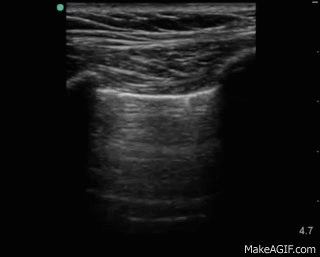

Indirekt ljusreflex innebär att du lyser i ett öga och letar efter pupillsammandragning i det andra. Om en patient har en skada i ett öga, eller om det inte går att öppna ögat på grund av ett hematom, kan den indirekta ljusreflexen utnyttjas. En linjär ultraljudsprob placeras transversellt över det skadade ögat (skydda ögat med en Tegaderm och applicera gel utanpå). Lys sedan i det friska ögat och leta efter pupillsammandragning på ultraljudet. Här är en tutorial från 5minSono: